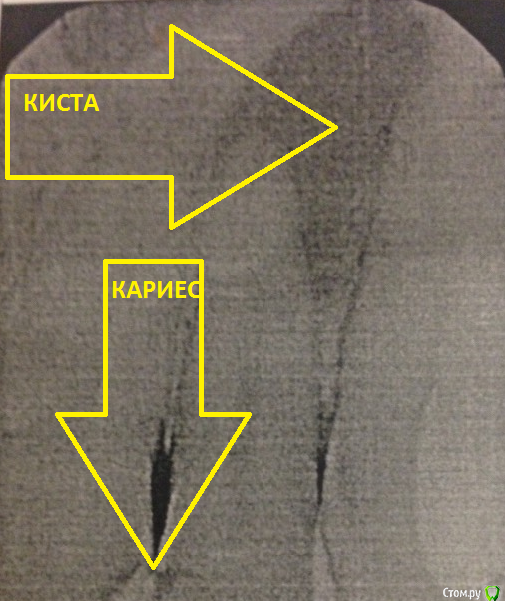

Balimali Опубликовано 8 июля, 2016 Поделиться Опубликовано 8 июля, 2016 Здравствуйте!Снимки 21,22,23,24 зубов.свежие. Была у своего врача 2мес назад,поменяли пломбу на 24 чтобы убедится нет ли кариеса,тк были жалобы на "невкусный вкус пищи" из межзубного пространства) итог-под старой пломбой все ок,с остальн зубами ок. Сейчас беспокоило:появилась труднопрощупываемая шишка в сааамом верху над 22(как лимфоузел),болей нет. Выводы стоматолога:21-лечить,22-огромная киста переходящая на 23,открывать лечить,,23-лечить,24-глуб кариес,депульпировать.я в шоке! Прокомментируйте пжлст снимкиП.с. За 2мес может образоваться тот кариес,котор есть сейчас? Или это врач не заметил его 2мес назад? Спасибо http://s020.radikal.ru/i715/1607/9d/2da533c47d67.jpg http://s012.radikal.ru/i320/1607/36/fa8561ea2463.jpg http://s019.radikal.ru/i644/1607/24/07ea48cdc2fe.jpg Ссылка на комментарий

___49___ Опубликовано 9 июля, 2016 Поделиться Опубликовано 9 июля, 2016 (изменено) Качество снимков не очень. Занимайтесь зубами . 22 лечение с наблюдением в динамике. Изменено 9 июля, 2016 пользователем ___49___ 1 Ссылка на комментарий